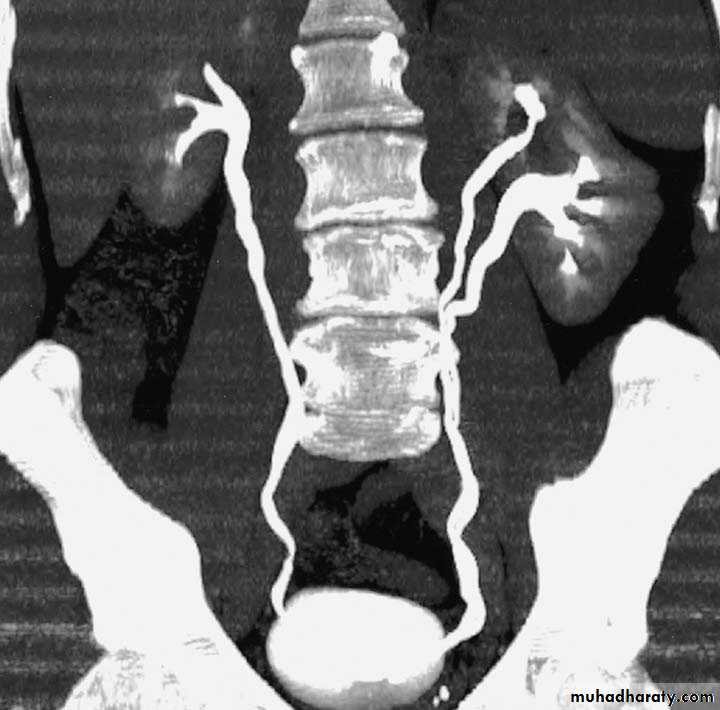

Crossed Renal Ectopia With and Without FusionHorseshoe Kidney

Found in 1:1000 necropsies and is more common in men.probably the most common of all renal fusion anomalies

The anomaly consists of two distinct renal masses lying vertically on either side of the midline and connected at their respective lower poles by a parenchymatous or fibrous isthmus that crosses the midplane of the body.

Fusion of the renal masses occurs early in embryonic life, so its ascent will be impeded by inferior mesenteric artery.

The kidneys are low located, mal rotated and pelves lie anteriorly

Diagnosis ultrasound, IVU, CT scan